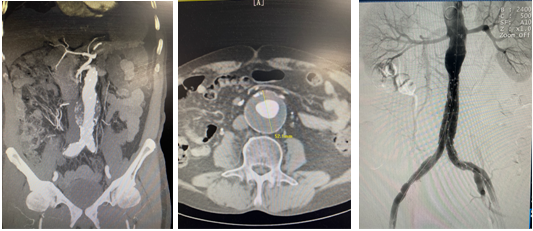

首例Yuranos腹主动脉覆膜支架治疗腹主动脉瘤合并右髂总动脉瘤手术,精准定位封闭瘤腔的同时保留患者盆腔血供,解除“双定时炸弹”,挽救患者生命。

本例腹主动脉瘤患者瘤颈长度3.6cm,瘤颈角度30.7°,瘤体直径5.28cm,瘤腔内血栓直径2.9cm,右侧髂总动脉瘤直径2.02cm。患者腹主动脉瘤瘤体直径较大,瘤腔内血栓较多,瘤体破裂及血栓脱落导致远端栓塞风险高,且合并右侧髂总动脉瘤,手术指征明确。术前在代毅主任指导下,医护团队积极完善相关术前检查,并组织了多次科内术前讨论,对手术方式、术中术后的风险及并发症、术后护理等均制定了详细计划及预案,确保手术安全顺利进行。本例手术难点在于合并右侧髂总动脉瘤,且累及右髂内动脉,术中、术后易发生远端型内漏、移植物移位、肾动脉闭塞等并发症。术中需栓塞右髂内动脉,所以必须精确定位左侧髂支支架的位置,保留左髂内动脉,确保盆腔血供。经充分评估患者病情及征得患者及家属同意后,详细制定手术方案,最终顺利完成手术。